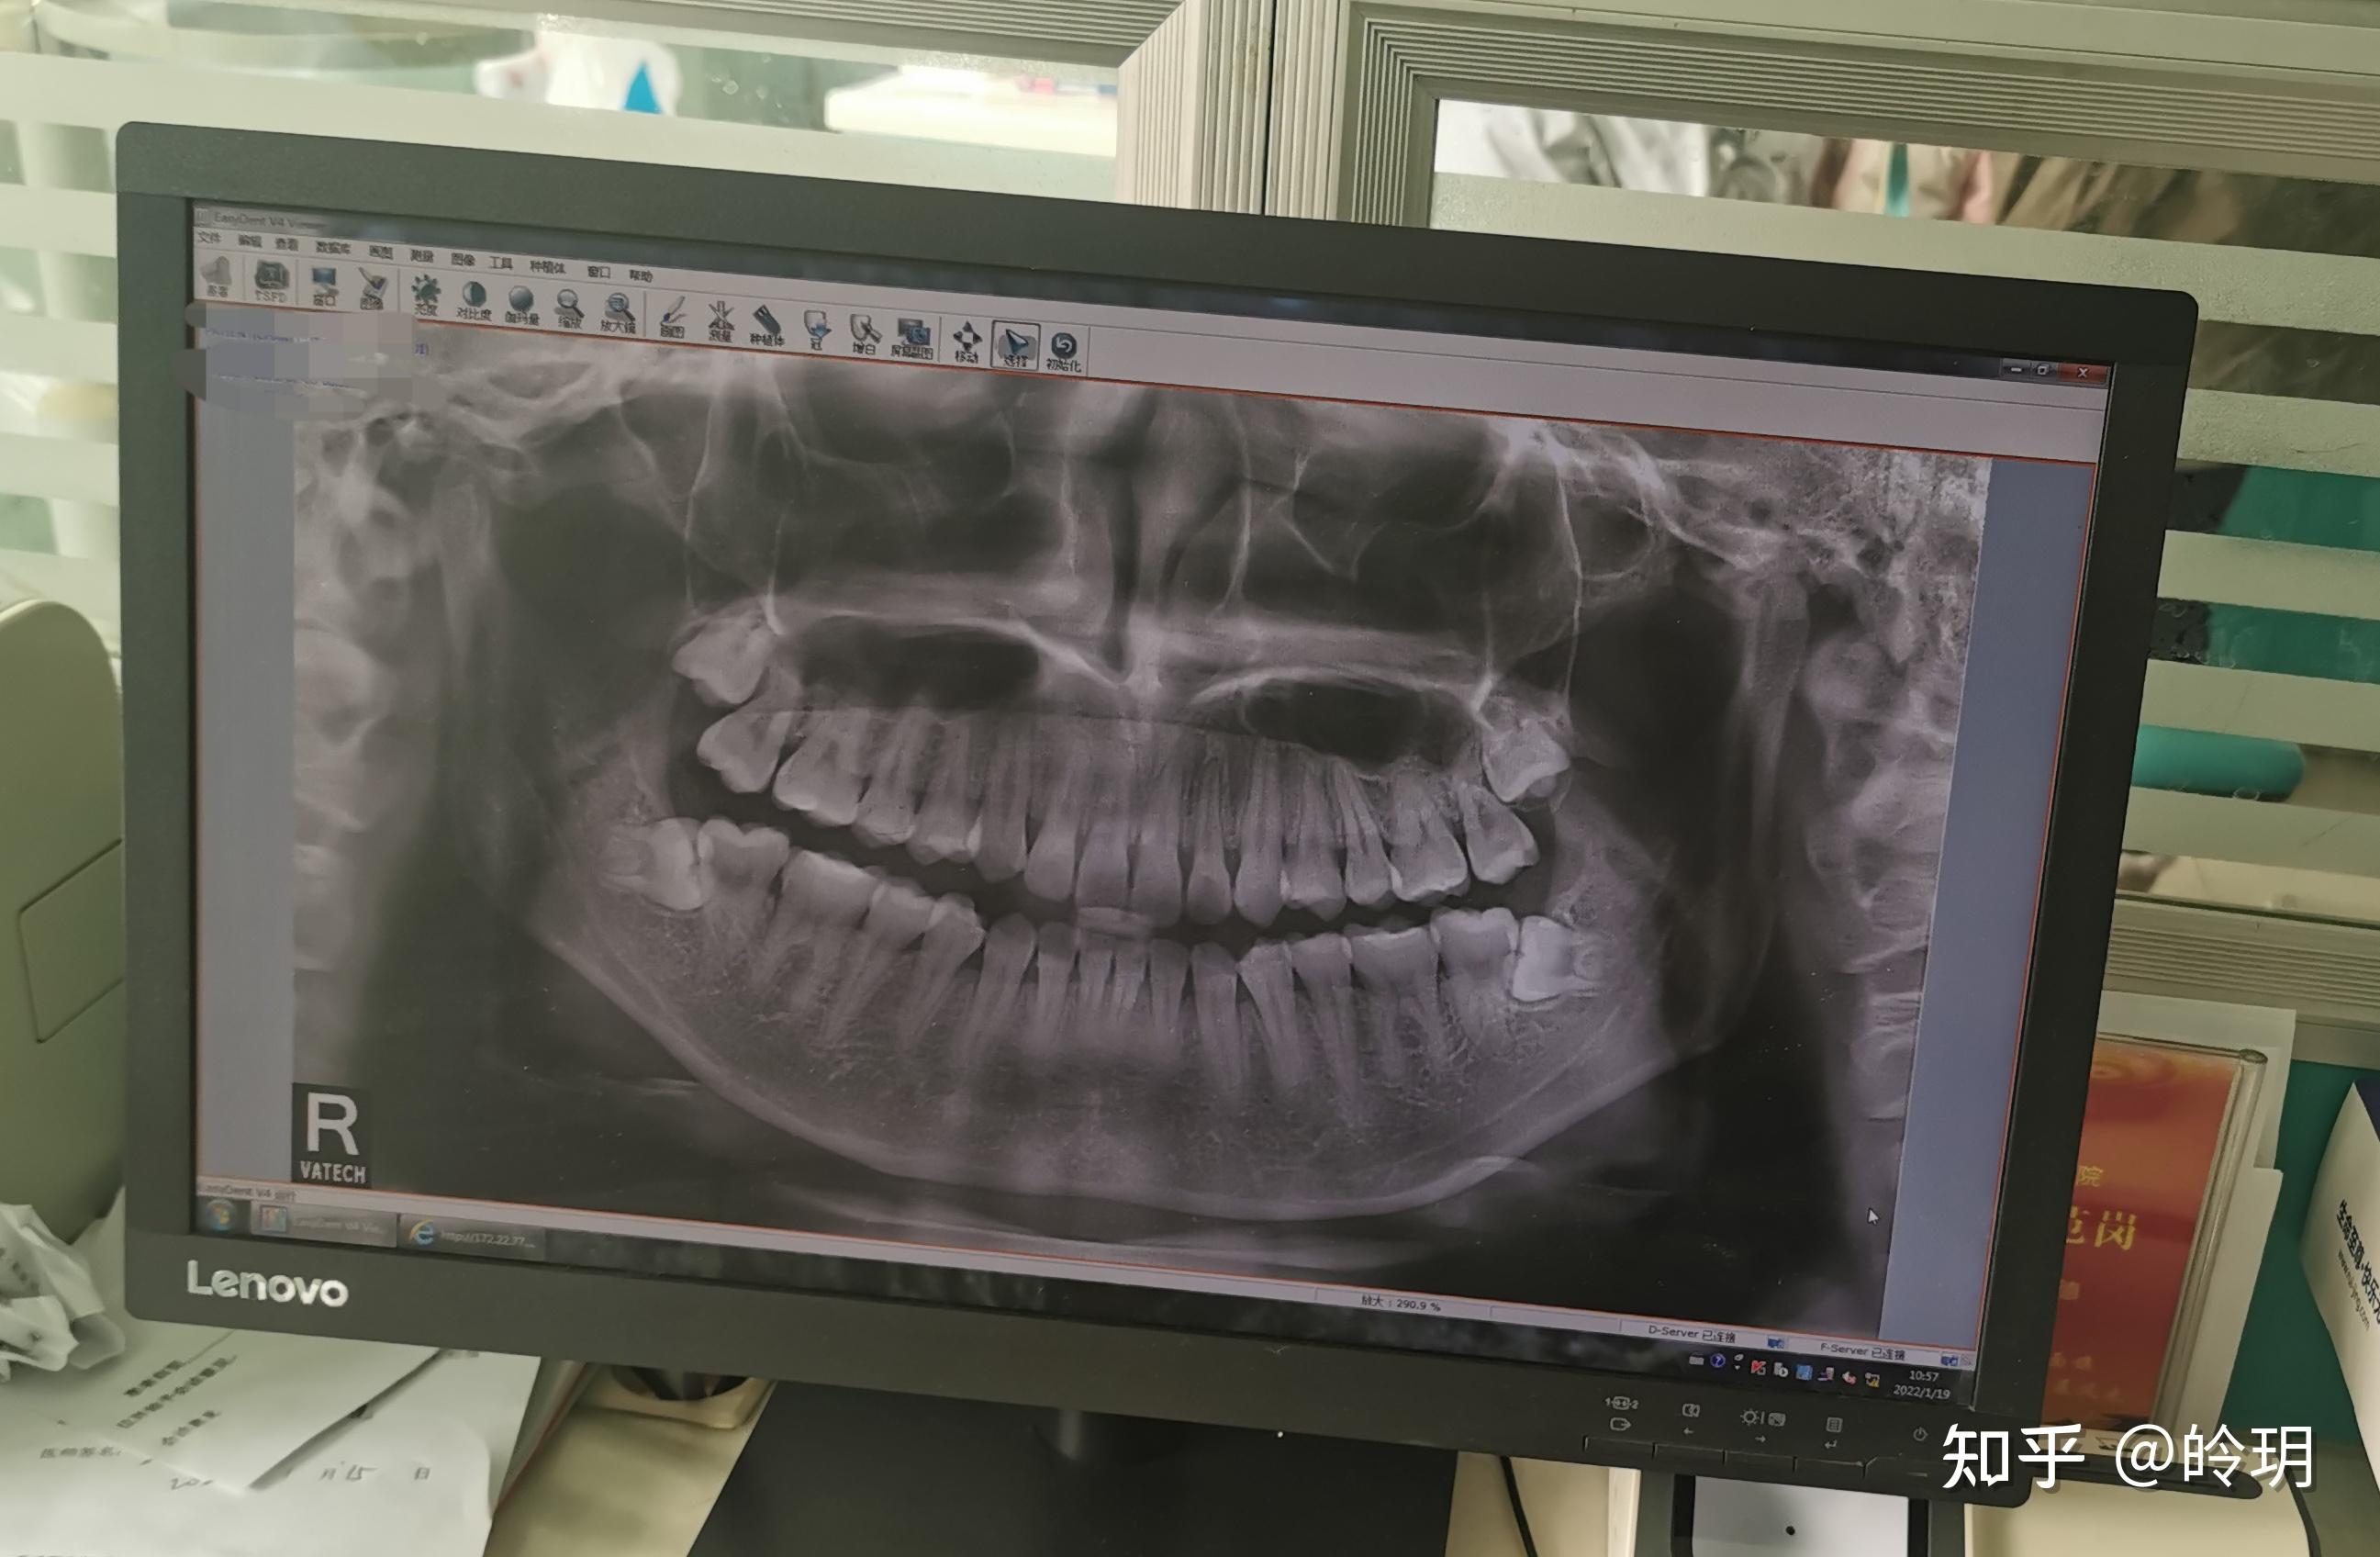

智齿,右下那个挨着神经在一个大型私立口腔医院拍了个牙齿ct花了280

为什么拔智齿医生让拍片子